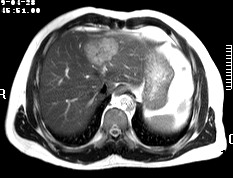

标题: CT19720:肝右叶血管瘤。肝左叶内侧段病灶考虑什么? [打印本页]

标题: CT19720:肝右叶血管瘤。肝左叶内侧段病灶考虑什么?

男,48岁,肝区不适月余,伴隐痛。

支持右叶血管瘤,左叶病灶考虑肝腺瘤。

1)不排除肝左叶肝癌。2)肝右叶血管瘤。

肝左叶炎性病变,肝癌待排。2)肝右叶血管瘤。

1.肝右叶血管瘤;2.肝左叶炎性假瘤?肝癌?建议穿刺活检.

右叶病灶典型,左叶病变慢性炎块

1、肝右叶血管瘤(典型)。

2、肝左叶病灶,强化不明显,疑炎性假瘤,建议结合临床并密切随访。

1、肝左叶炎性病变,肝癌待排。

2、肝右叶血管瘤。

肝左叶脓肿,肝癌待排。2)肝右叶血管瘤